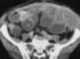

Small bowel obstruction

Bowel obstruction, also known as intestinal obstruction, is a mechanical or functional obstruction of the intestines which prevents the normal movement of the products of digestion. Either the small bowel or large bowel may be affected. [Source: Wikipedia ]